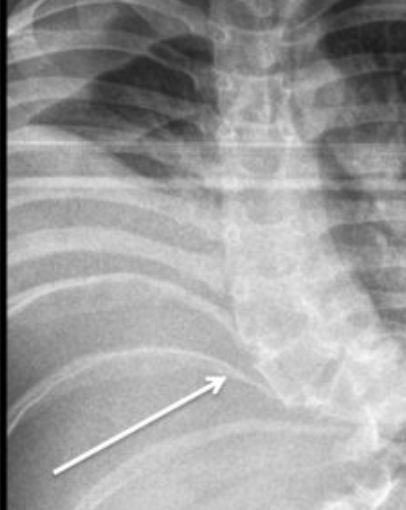

Absent thoracic pedicles are a key feature of this syndrome

Camptomelic dysplasia

-congenital dwarfism associated with potentially fatal respiratory insufficiency

- anteriorly bowed tibias with cutaneous dimpling, anterolaterally bowed femurs, thoracic kyphoscoliosis, hypoplastic scapulas,